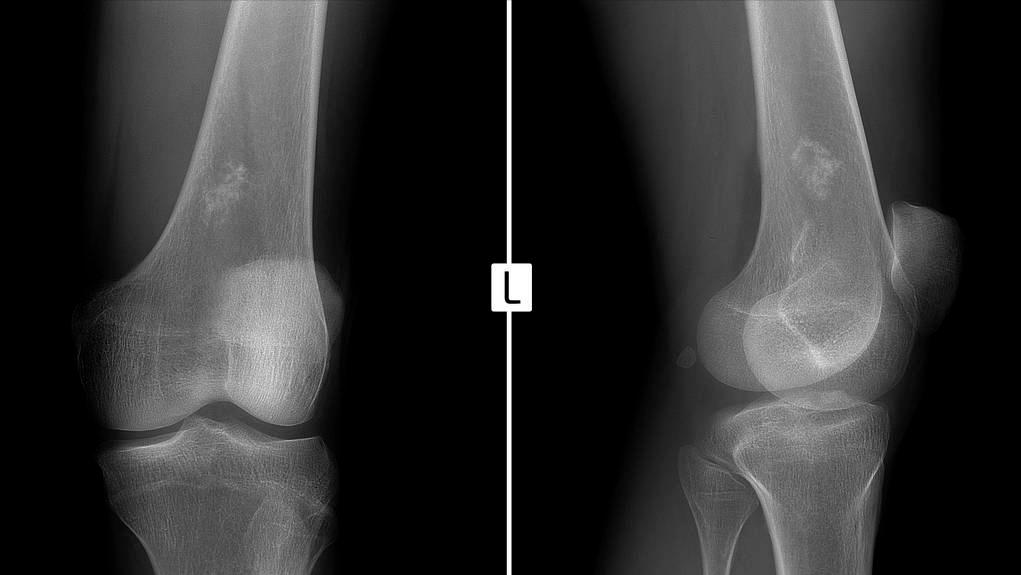

张阿姨的老伴看了看,要求她第二天到医院做个检查。可是张阿姨觉得这个包块没有痛,也没有痒,不是特别乐意去医院。老伴顾不上她的反对,第二天连同儿子一起将她带到医院就诊,经过拍片检查,发现她这个包块是骨肉瘤,需要及时做手术治疗。

肉瘤引起的不适症状,需要根据发病部位来判定,比如肉瘤可以根据不同组织的来源分成纤维肉瘤、肉瘤、骨肉瘤、平滑肌肉瘤、骨巨细胞瘤、血管肉瘤等。无论是哪一种肉瘤,其典型症状主要包括肿块、疼痛、溃疡,有些还会出现全身症状。

除此以外,肉瘤如果生长在关节附近,还会对关节的活动造成影响,引起肢体感觉异常或者运动障碍。